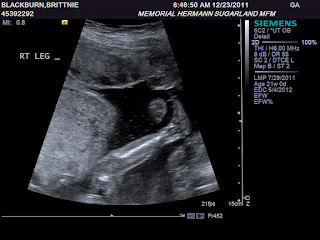

A few pictures from our 20 week anatomy scan:

| Close up of her leg and foot |

Our little girl currently weighs 13 ounces and the ultrasound tech and Dr both agreed she looked perfect so far and they saw no concerns via the ultrasound scan. Praise God!!